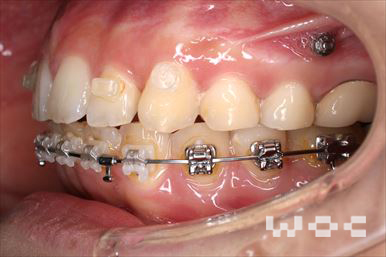

出っ歯エッジワイズ装置

特に装置の希望はなかったので、エッジワイズ装置を選択。

歯の移動量が大きいので歯根吸収の可能性がありましたが、目立った吸収は見られませんでした。-

- 年齢:17歳女性

- 主訴:出っ歯、前歯のガタガタが気になる

- 基本矯正料金:78万円

- 治療期間:1年2ヶ月

- 抜歯部位:上顎両側第一小臼歯